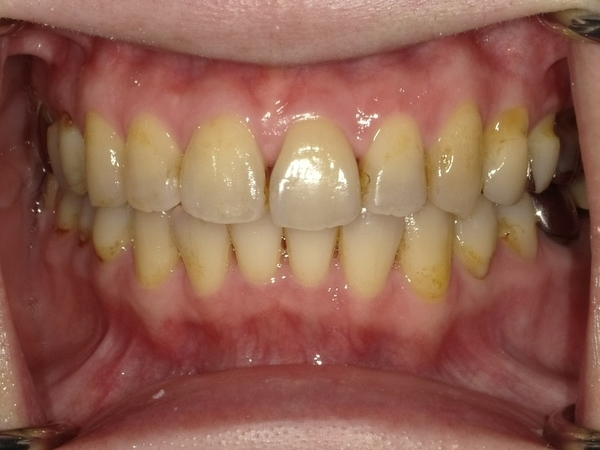

Before After

●ご相談内容:前歯が曲がっている●矯正の種類:マウスピース型「矯正インビザラインGO」●治療期間:18週●治療費用:66万円(税込)